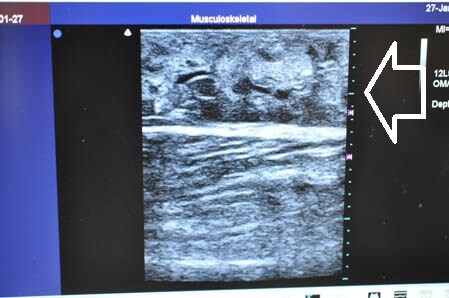

画像上しっかりと皮下脂肪は根こそがれており

間違いなく患者様のご期待にはそえられると思います。